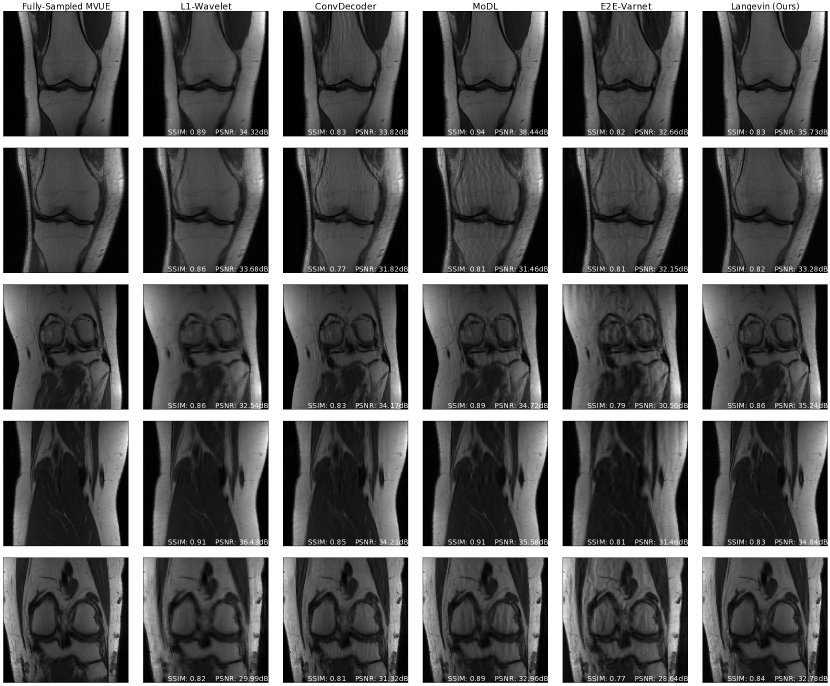

Refer to caption

Figure 1: Comparison of reconstruction methods for in-distribution, sampling-shift, and anatomy-shift images. All methods and hyperparameters were optimized on T2-weighted brain scans with a vertical sampling mask, and tested at higher accelerations, horizontal masks, and on knee & abdomen scans. Our reconstructions are competitive with state-of-the-art methods, and introduce fewer artifacts out of distribution. All measurements are multicoil k-space from the NYU fastMRI dataset and the supervised baselines are trained from scratch on MVUE targets for a fair comparison.

Our main results are succinctly summarized in Figure 1: we achieve equivalent reconstruction performance using a reduced training set when evaluated in-distribution and are robust when evaluated out-of-distribution.

Figure 1 (top three rows) shows qualitative results and Figures 2a & 5a respectively show PSNR & SSIM values, for the case where there is no mismatch between the training and inference sampling patterns. As the baselines were trained to maximize SSIM at R=3& 6𝑅36R=3\;\&\;6, we see that they achieve better SSIM scores than us at these accelerations, although there is clear aliasing in the baselines at R=6𝑅6R=6. We achieve better PSNR values at these accelerations, which supports the claim that our method does not overfit to a particular metric (Theorem 3.4). This also highlights the importance of qualitative evaluations in medical image reconstruction and the limitations of existing image quality metrics [65]. From the third row of Figure 1, and Figures 2a & 5a, we notice that our method surpasses baselines at higher accelerations.

Figure 1 (fourth row) shows qualitative reconstructions when the measurements are obtained from an equispaced, horizontal sampling mask, with an acceleration factor R=3𝑅3R=3. It can be observed that the reconstructions output by E2E-VarNet show aliasing artifacts. Based on the statistical results in Figure 2b & 5b, our method retains its performance.

Finally, Figures 2d & 5d show PSNR and SSIM scores obtained on fastMRI knee reconstructions, while Figure 1 (bottom row) shows the accompanying qualitative plots. This anatomy is challenging especially because of the poor signal-to-noise ratio conditions, which can be seen even in the ground-truth image. It can be noticed that this is the most severe shift for all methods, but our approach still shows the best performance at R=2,4𝑅24R={2,4} and a significantly lower variance. Appendix D shows more examples of knee reconstructions with and without fat suppression, and Figure 20 shows metrics on fat suppressed knees.